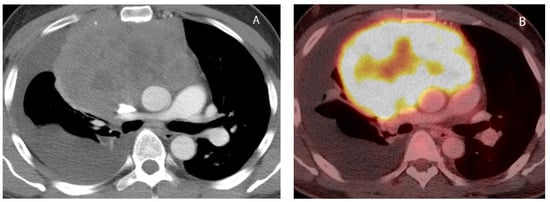

6. Lymphoma